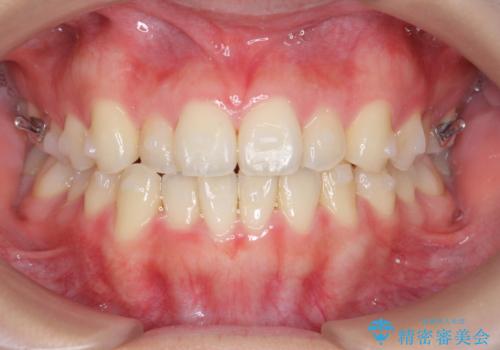

ガタつきの改善 マウスピース矯正治療

- 歯のがたつきの改善を求めて、矯正治療を希望され来院されました。

少量の歯のディスキング、歯列弓拡大、アタッチメントを装着することで審美的な歯列へとマウスピース矯正インビザラインを用いて治療を行います。

マウスピース矯正は装着時間の遵守が非常に大切ですが、しっかりと20時間/日以上の装着を守っていただいたおかげで良好な治療結果を得ることができました。